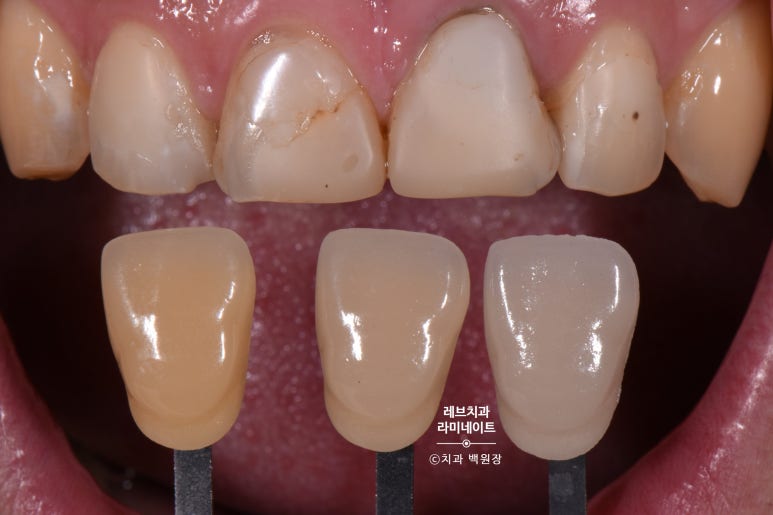

치료하기 전 치아의 색상을 채득해 두어야 합니다.

VITA shade guide를 사용하여, 치아를 깎아내기 전에 색상을 미리 기록해둡니다.

치아를 일부 다듬어드린 뒤 찍은 사진입니다.

치아가 다소 작아졌다고 생각하실텐데요, 기존에 치료되어 있었던 불필요한 레진들을 제거했기 때문입니다.

남아있는 old resin은 세라믹 재질의 레브네이트 엑스퍼트를 붙일 때, 완벽한 접착을 방해하기에 모두 깨끗이 정리되어야만 한답니다.